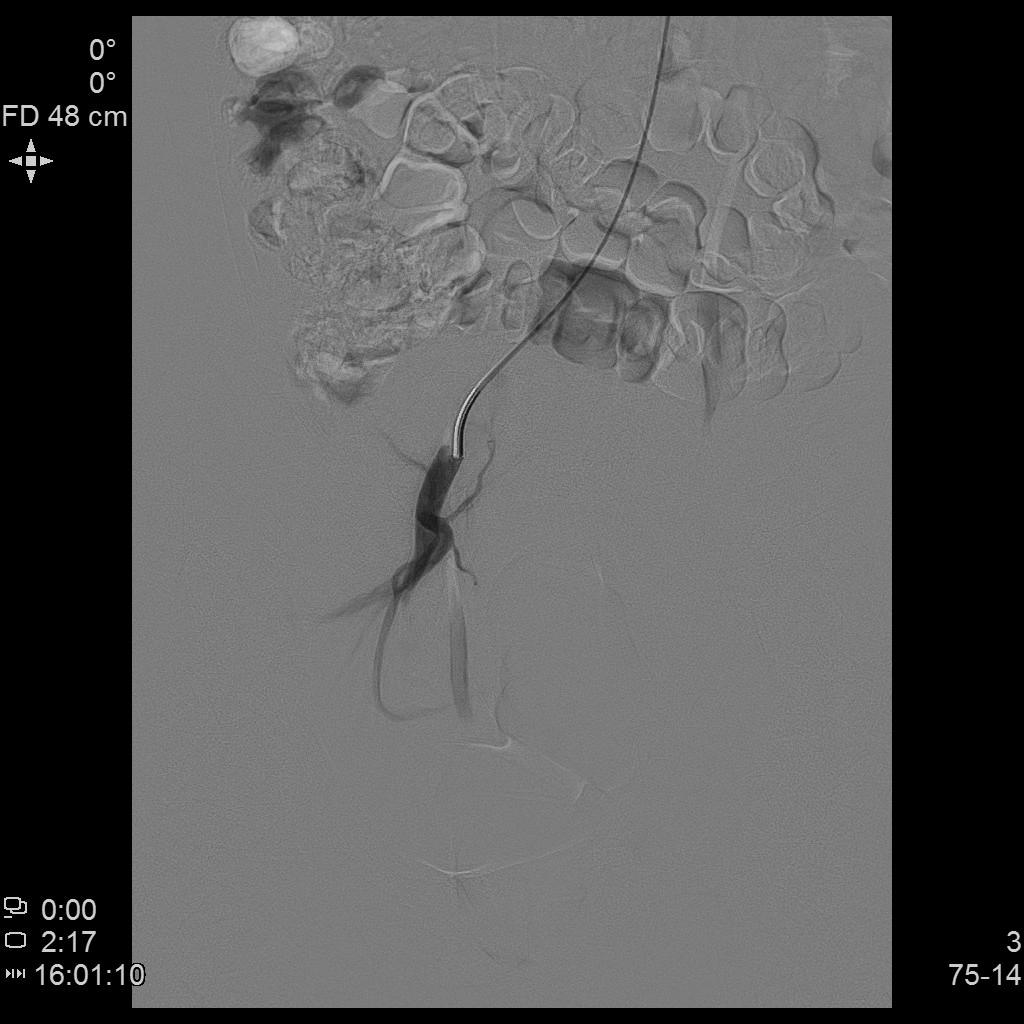

- DSA下行双侧子宫动脉栓塞治疗。

左侧子宫动脉造影

右侧子宫动脉造影

- 经桡动脉入路置入导管造影显示双侧子宫动脉明显增粗,染色丰富,子宫明显增大。

右侧髂内动脉造影

左侧髂内动脉造影